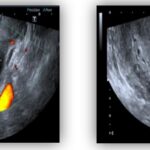

Se presenta el caso de una paciente de 56 años, posmenopáusica, con antecedente de Ca mama en tratamiento con anastrozol, anexectomía derecha por cistoadenoma seroso. Consulta por sangrado uterino anormal de un mes de evolución. Se realizan exámenes complementarios, como ecografía transvaginal y resonancia magnética pélvica, para evaluar la lesión; se categorizó como ORADS IV.

El artículo concluye resaltando la importancia de considerar a la ecografía como el primer método diagnóstico, y con la RMN de pelvis se estratifica el riesgo de malignidad. Sin embargo, su confirmación diagnóstica concluye con el resultado anatomopatológico posquirúrgico en la mayoría de los casos.

Se presenta el caso de una paciente de 56 años, posmenopáusica, con antecedente de Ca mama en tratamiento con anastrozol, anexectomía derecha por cistoadenoma seroso. Consulta por sangrado uterino anormal de un mes de evolución. Se realizan exámenes complementarios, como ecografía transvaginal y resonancia magnética pélvica, para evaluar la lesión; se categorizó como ORADS IV.

Resaltamos la importancia de considerar a la ecografía como el primer método diagnóstico, y con la RMN pelvis se estratifica el riesgo de malignidad. Sin embargo, su confirmación diagnóstica concluye con el resultado anatomopatológico posquirúrgico en la mayoría de los casos.

Anexos (imágenes)